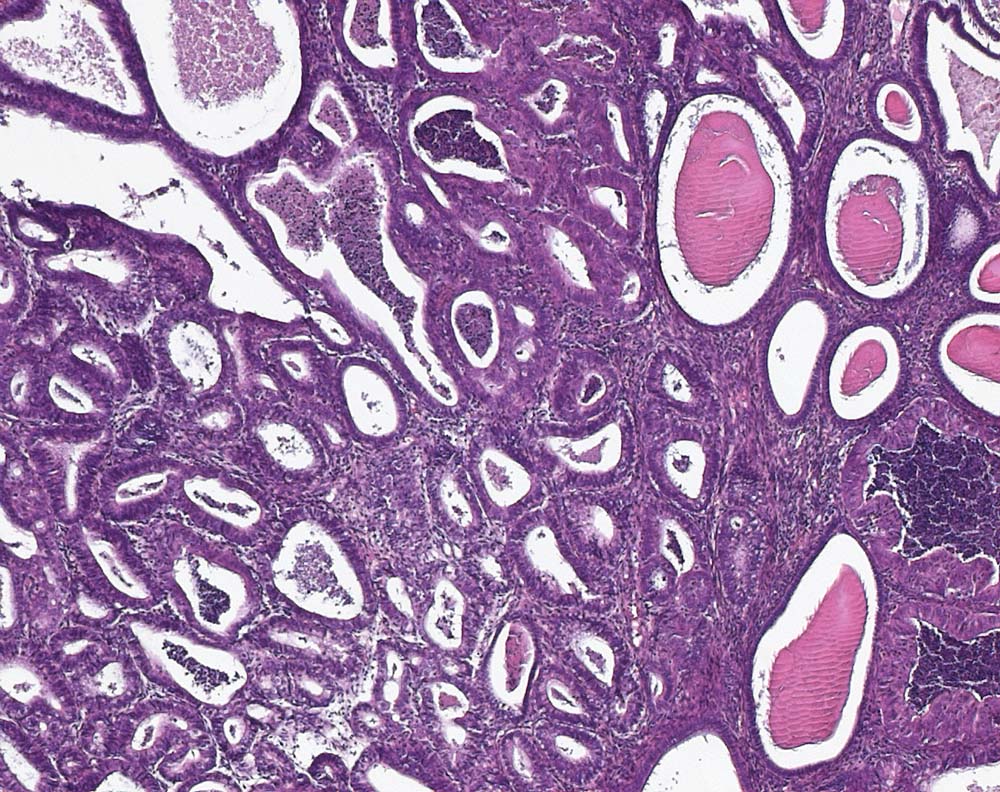

Endometriale intraepitheliale neoplasie (EIN)

Endometriale intraepitheliale Neoplasie: Umschriebener Herd sehr dicht beeinanderliegender Endometriumdrüsen ausgekleidet von atypischem Epithel, welches sich zytologisch deutlich vom Epithel der nicht neoplastisch transformierten Drüsen unterscheidet. Im Gegensatz zum endometrioiden Adenokarzinom ist zwischen den Drüsen der EIN noch wenig Stroma erkennbar.

Endometriale Hyperplasie, Verdacht auf Neoplasie im Uteruskorpus. Postmenopausen-Blutung.